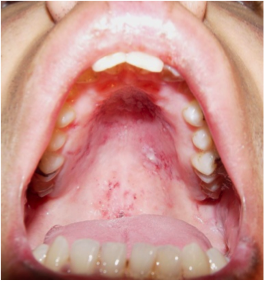

Dermatomyositis